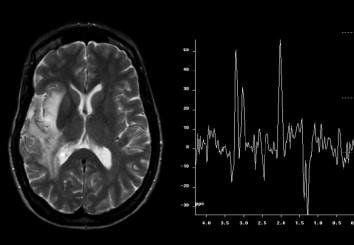

Chụp cộng hưởng từ phổ não (spect tính rography)

Chụp cộng hưởng từ phổ (MRC) là kỹ thuật dùng từ trường và sóng RF để xác định nồng độ các chất chuyển hóa trong mô sống. Theo đó, cộng hưởng từ phổ não thường sử dụng các chất chuyển hóa chứa P, Na, K, C, N, F để đánh giá nồng độ các chất chuyển hóa để thu được phổ với các đỉnh tương ứng là nồng độ các chất trong vùng khảo sát.